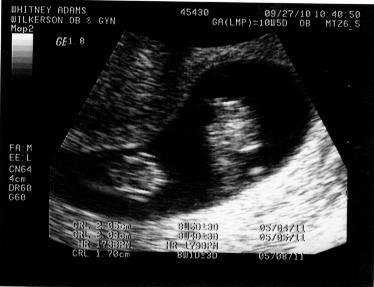

How Far Along: 9 Weeks

Size of our babies: Our twins are the size of grapes this week.

Best Moment this week: Seeing both our babies and their heartbeat on the ultrasound this week.